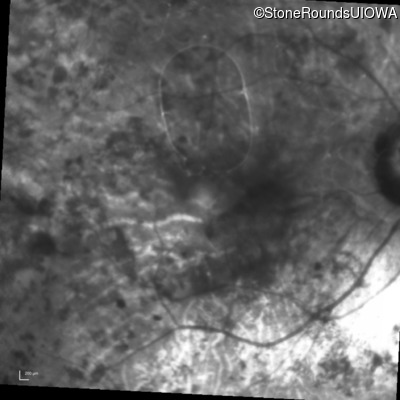

Infrared Fundus Photograph - Right - 3/120

Exemplar

Infrared Fundus Photograph - Left - 20/63 +2